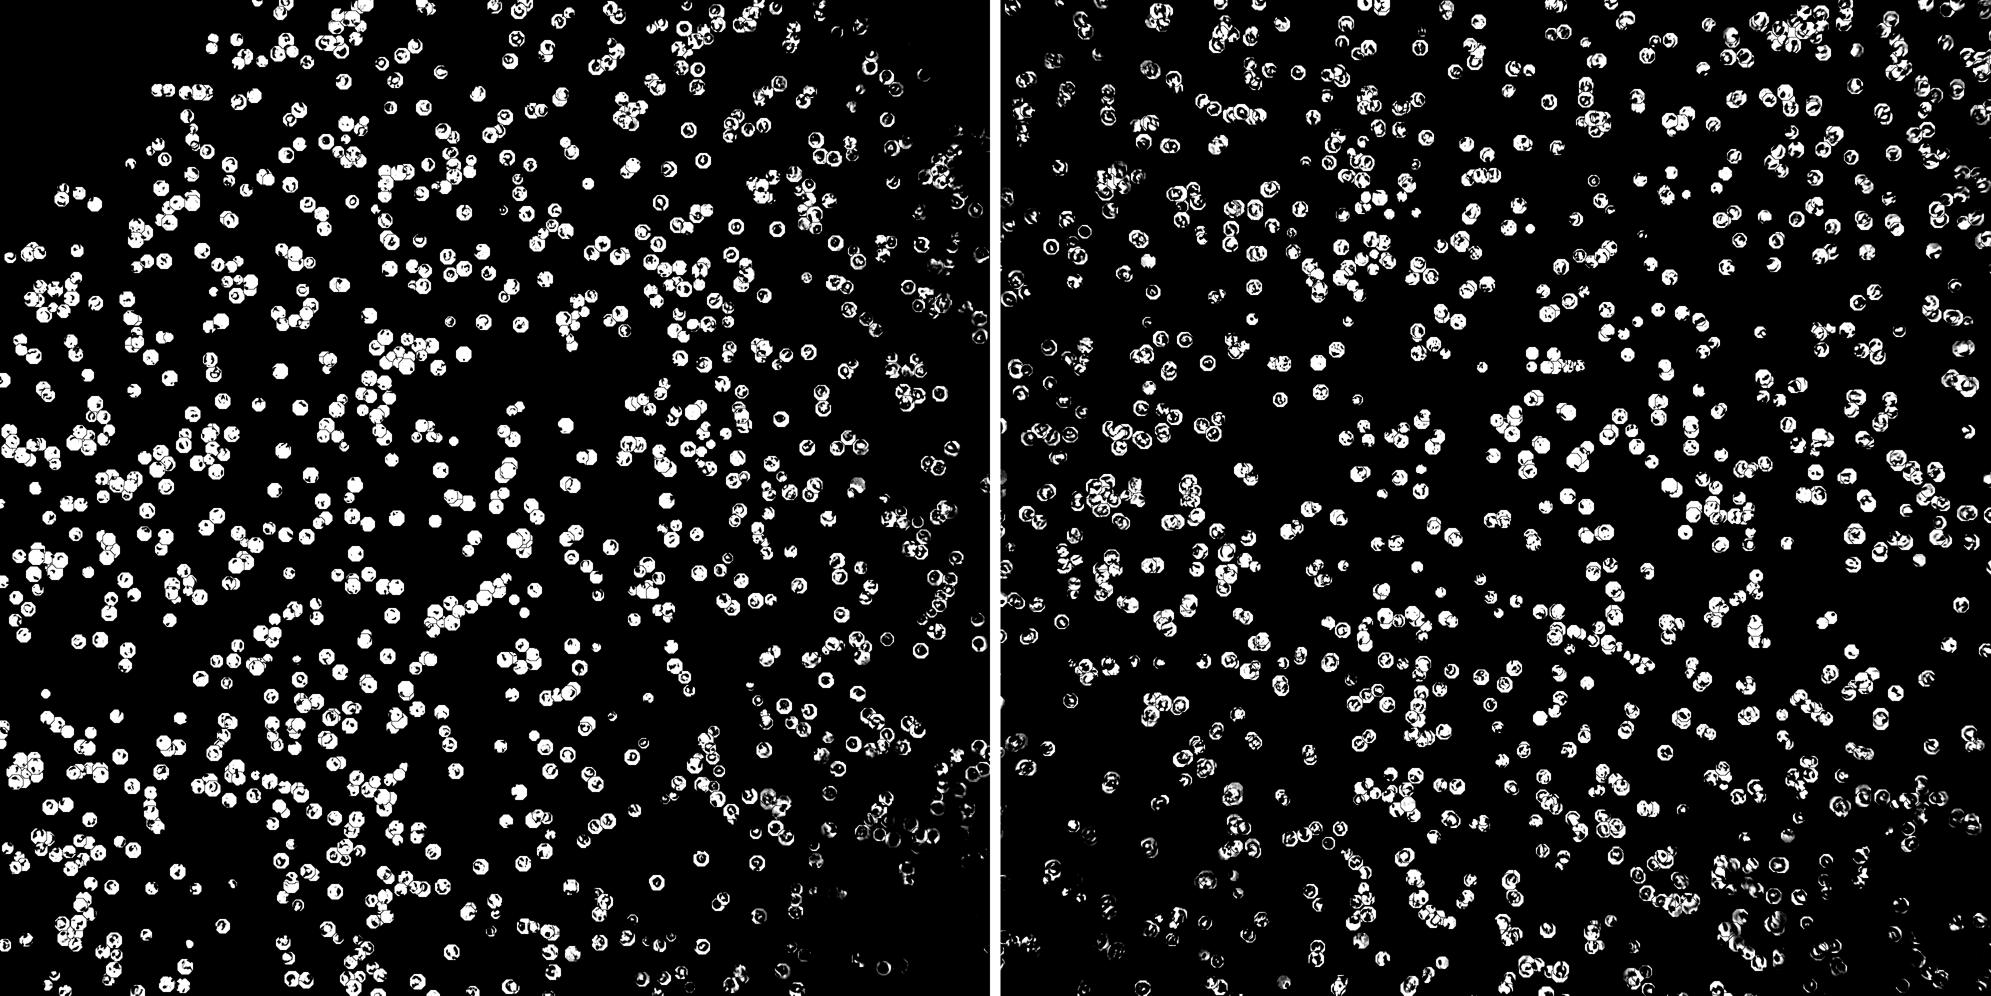

Phase contrast image

Peripheral blood lymphocytes

Inflammatory Disease

Cell populations before and after treatment